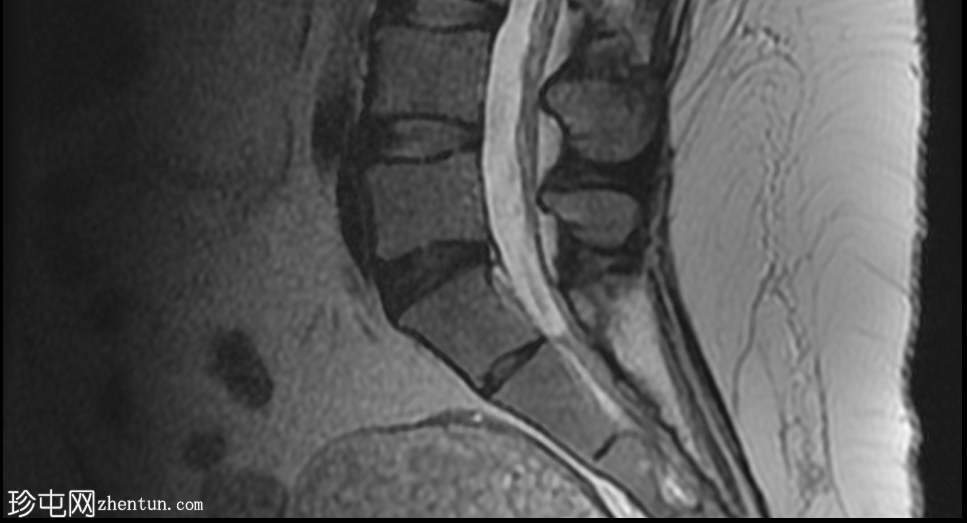

MRI

矢状位

T1加权像

T2加权像

盆腔可见部分囊性肿块,内含脂肪球。

该患者主诉左下腹疼痛。影像学检查发现盆腔内有一囊性肿块,可见多个脂肪球。影像学检查未发现扭转或破裂的迹象。建议进行盆腔MRI随访检查。